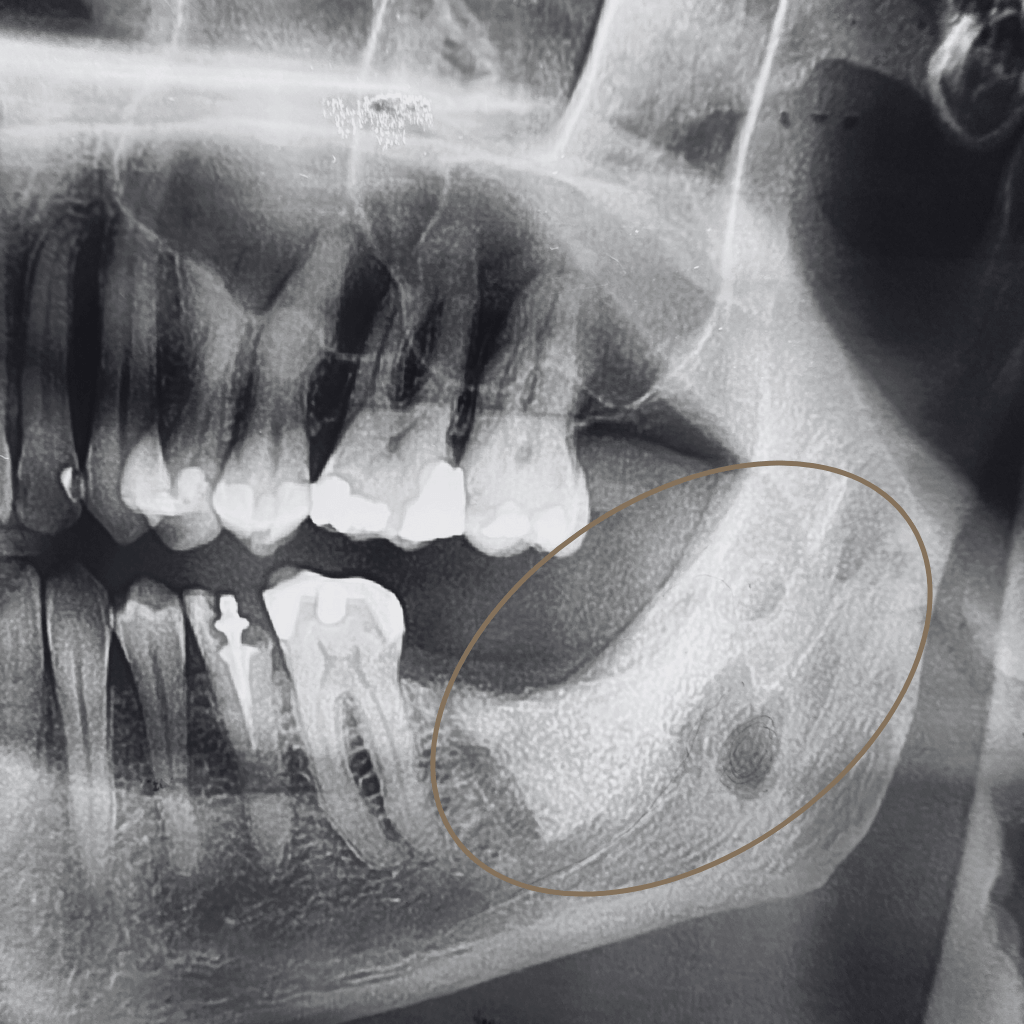

Промени в костта или меките тъкани на лицево-челюстната област изискват прецизна диагностика и ясен терапевтичен план. Навременното установяване на характера на лезията е ключово за правилното лечение и прогнозата.

В лицево-челюстната област туморите и кистите могат да засегнат костните структури, венците, езика, бузите и други тъкани на устната кухина. В клиничната практика се срещат както доброкачествени образувания, така и предтуморни или злокачествени състояния, които изискват навременна и точна диагностика.

Извършва се клиничен преглед и анализ на образните изследвания, за да се оцени локализацията, обемът и характерът на формацията.

• Неясни находки при образни изследвания